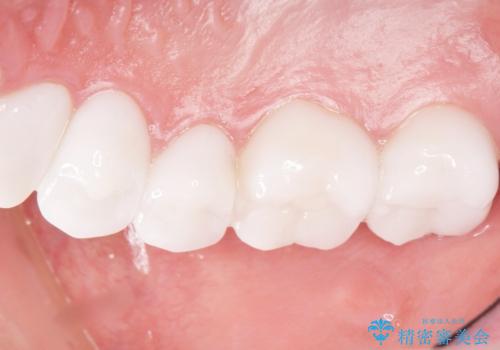

憧れのヴィジュアル系バンドマンのような白い歯になり、喜んで下さいました。

不適なレジン充填によるデコボコがなくなったことで歯磨きしやすくなり、また気にされていた咬み合わせも良くなり、ご満足頂けました。

クラウンの種類:オールセラミッククラウン スタンダード

シェード:NW0